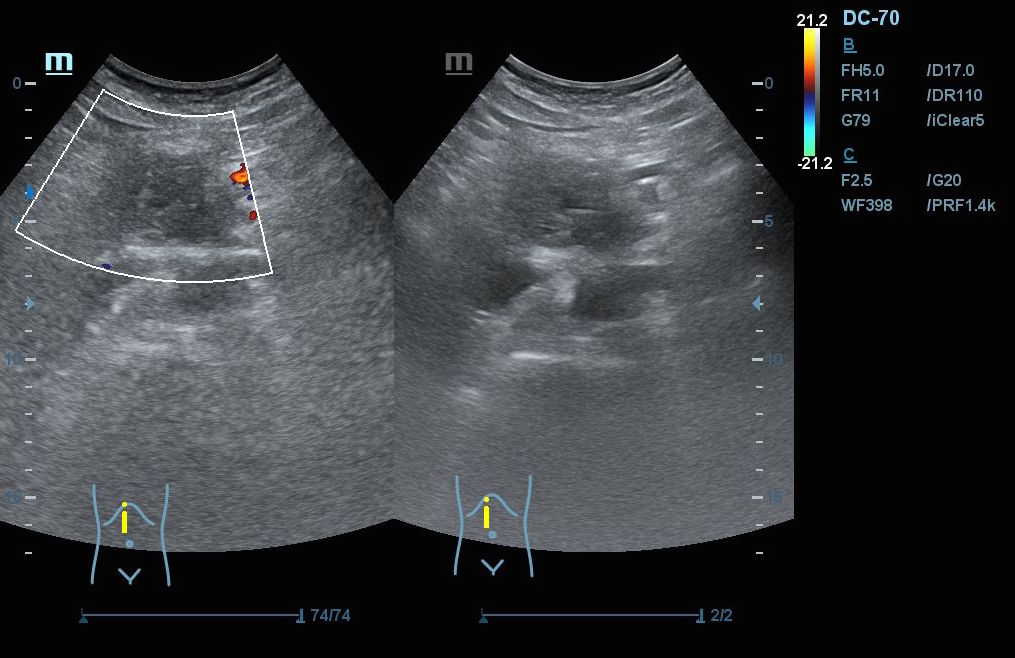

Hallazgos ecográficos: En el epigastrio se observa una imagen anecoica tubular, sin captación en Doppler, con un diámetro mayor a 2 cm, que sugiere una dilatación del colédoco (imagen 1). La vesícula biliar se encuentra completamente distendida y hepatizada, con una imagen en «doble cañón de escopeta» sugestiva de colestasis (imagen 2). En los cortes longitudinales se identifica una masa anterior a la aorta en el corte paramedial izquierdo, aparentemente localizada en el cuerpo del páncreas (imagen 3). En los cortes transversales se observa una masa que afecta tanto al cuerpo como a la cabeza del páncreas (imagen 4).